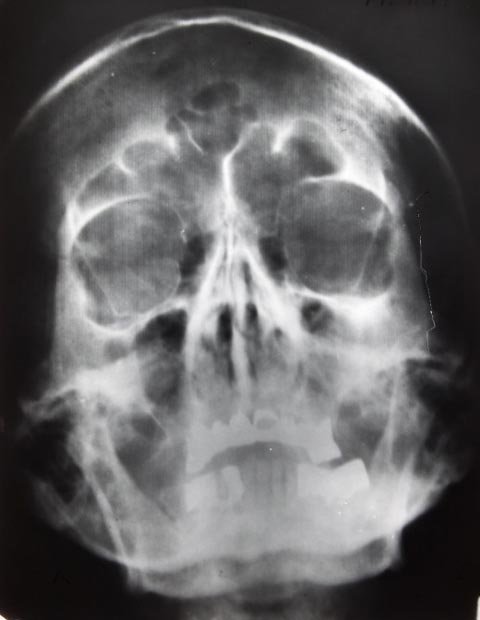

Một tập báo cáo giải mật gồm 47 trang có trích dẫn các cuộc phỏng vấn sâu rộng với 6 bác sĩ trưởng chuyên chăm sóc sức khỏe cho Hitler (mỗi bác sĩ chuyên trách một lĩnh vực chữa trị khác nhau) cũng như 10 tấm phim X-quang chụp hộp sọ và kết quả nhiều cuộc điện não đồ kiểm tra hoạt động não của lãnh đạo Đức Quốc xã.

![]() |

| Một phim chụp X-quang hộp sọ của trùm phát xít Đức. Ảnh: HuffingtonPost |